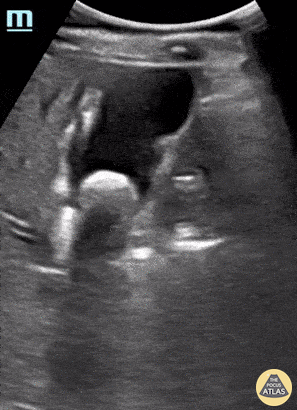

Biliary - Cholelithiasis

An elderly female presented to the emergency department reporting abdominal pain. POCUS seen here revealed the presence of a gallstone within her gallbladder with shadowing; and a notable absence of findings consistent with cholecystitis including gallbladder sludge, wall thickening, and/or ductal dilatation. This enabled appropriate triage of this patient to outpatient follow-up rather than considering immediate surgical intervention. Rupinder Sekhon, MD & Peter Biggane, MD Central Michigan University, Emergency Medicine